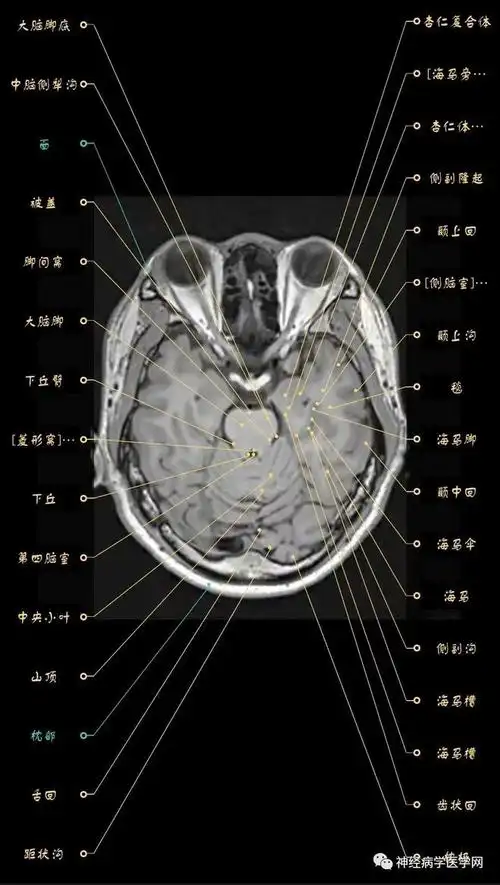

超赞!颅脑大体及磁共振断层解剖(轴位)

高清颅脑mri最全轴位影像解剖人手一册

mri颅脑横断面解剖图谱

这个高清颅脑断层解剖图谱实在太棒了!【磁共振 大体标本】